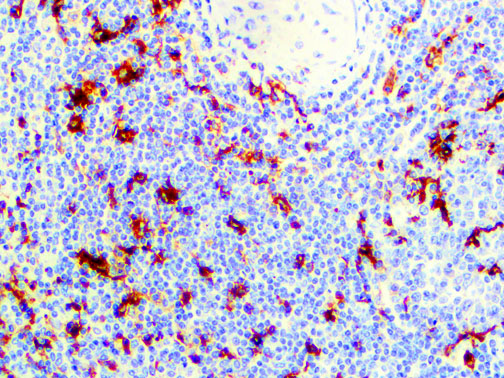

It is the ICU physician who is most likely to witness one of the deadliest manifestations of the abnormal immunological response, the cytokine storm syndrome (CSS). This response is also referred to by some as the cytokine release syndrome (CRS). CSS is characterized by continuous activation and expansion of macrophage and lymphocyte populations, which secrete large amounts of cytokines, causing the cytokine storm. This massive cytokine release is akin to hemophagocytic lymphohistiocytosis (HLH) disease, a syndrome characterized by initial unchecked and persistent activation of cytotoxic T lymphocytes and NK cells.

Clinical and laboratory manifestations of HLH include fever, enlarged liver and/or spleen, neurologic dysfunction, coagulopathy, liver dysfunction, cytopenias (i.e., low levels of erythrocytes, leukocytes, and/or platelets), hypertriglyceridemia, hyperferritinemia, hemophagocytosis, and eventually diminished NK cell activity as the immune system becomes progressively paralyzed. HLH can be familial (primary HLH) or secondary to another disease process (sHLH), such as rheumatic disease, in which it is referred to as macrophage activation syndrome (MAS, characterized by elevated ferritin).